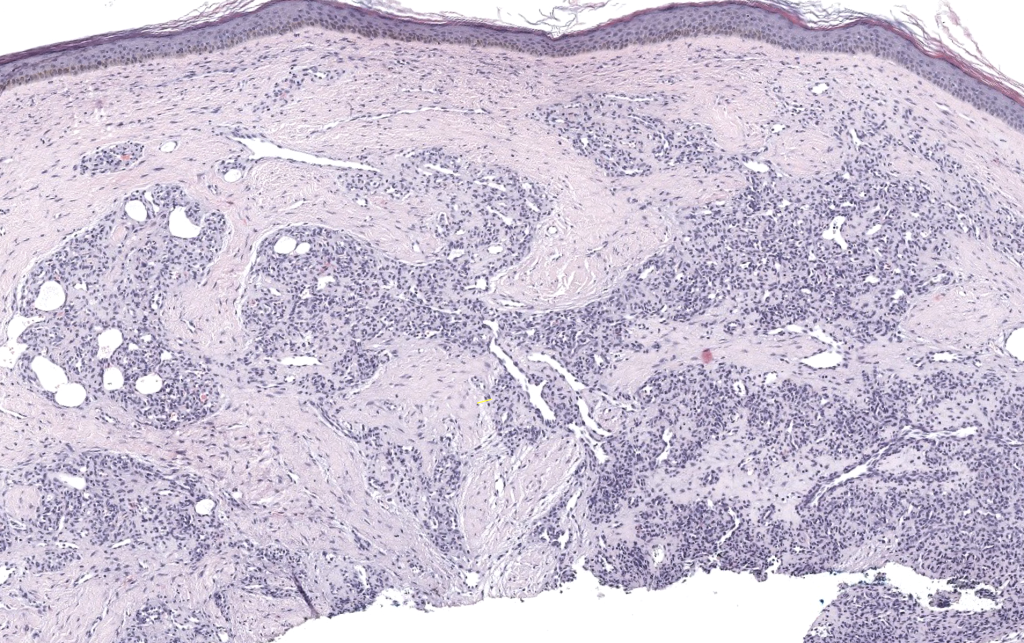

Neoplasia benigna perivascular originada en las células musculares lisas modificadas del cuerpo glómico neuromioarterial (cuerpo de Sucquet-Hoyer), estructura arteriovenosa especializada en la termorregulación digital. Se localiza típicamente en la dermis y tejido celular subcutáneo de los dedos, especialmente en la región subungueal. Samaniego 2009, Hazani 2008, Smith 2019 - Glomangioma / malformación glomovenosa (glomuvenous malformation, GVM)

- Tumor glómico sólido

- Glomangioma (tumor glómico con componente vascular prominente)

- Glomangiomioma (con mayor componente de músculo liso) Samaniego 2009, Smith 2019